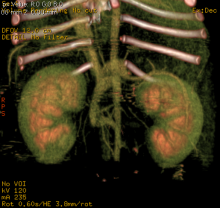

Subcutaneous Ureteric Bypass or SUB placement in Cats

Subcutaneous Ureteric Bypass or "SUB" placement By Tim Charlesworth Ureteric obstruction is an increasingly diagnosed condition in cats with ...